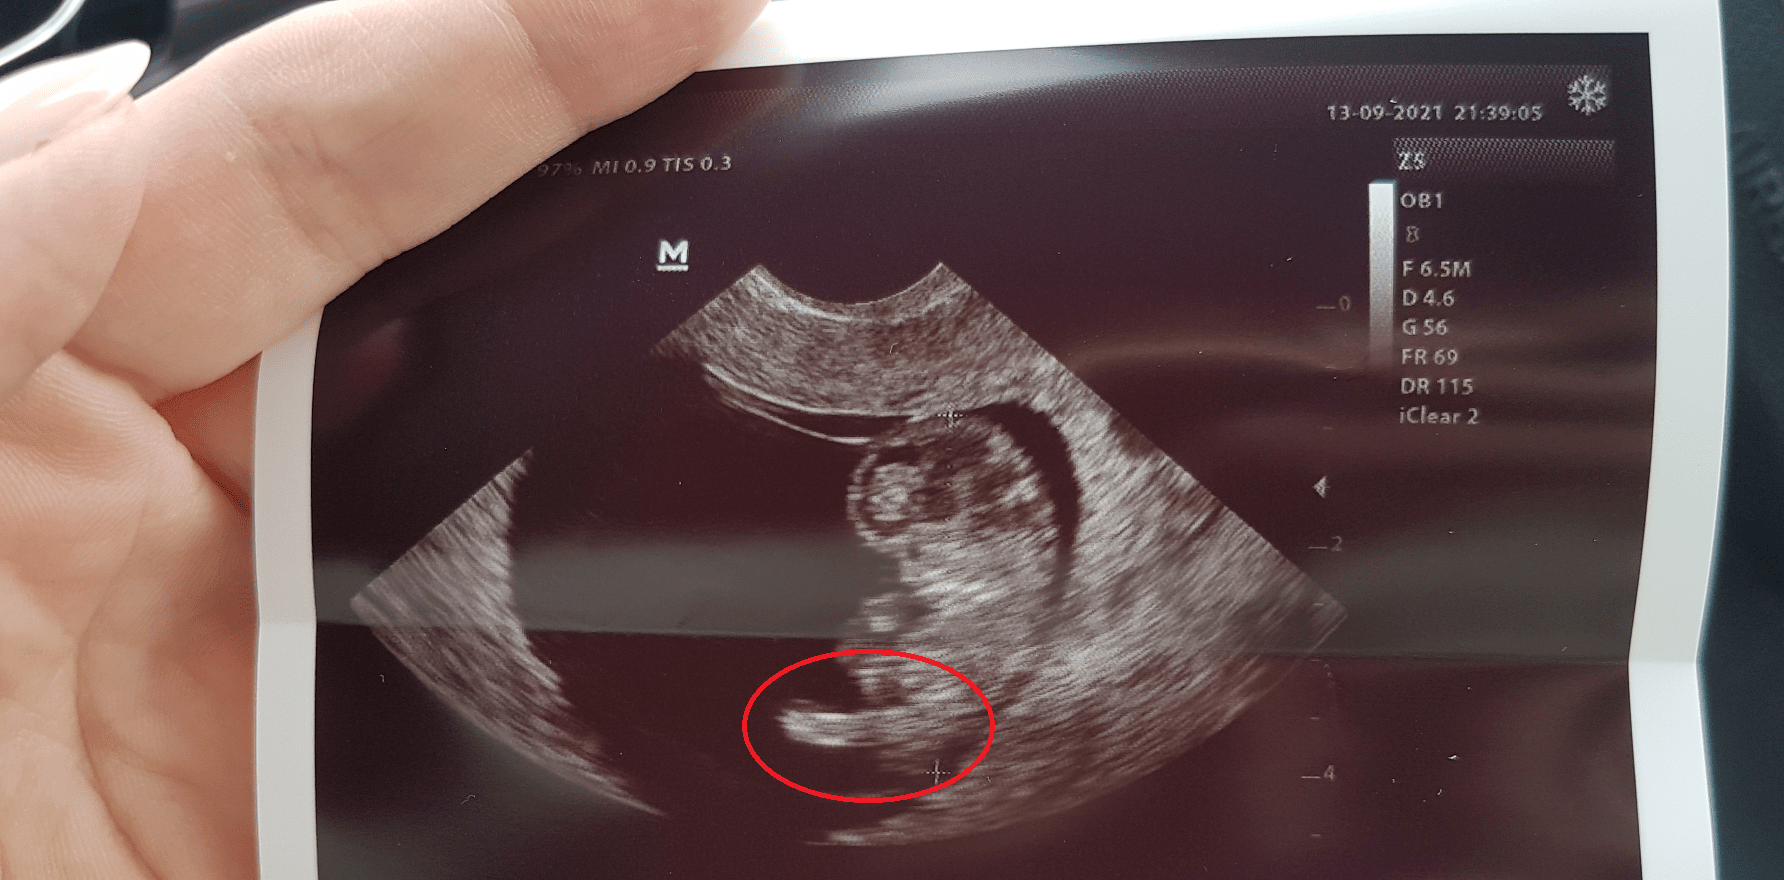

Według opisów tego tygodnia i rozwoju dziecka to jeszcze nie wiadomo czy chłopiec czy dziewczynkaNo ja teżciekawe czy to to czy za szybko by zobaczyć

dobre! hahahaMój mąż w poniedziałek po USG do mnie 'to na dole to siusiak?' a ja 'nie, to noga'

moj jak mu pokazuje zdjecie usg i tlumacze, ze tu glowa, tu ręce to on patrzy i mówi, że on i tak nic tam nie widzi hahahaMój mąż w poniedziałek po USG do mnie 'to na dole to siusiak?' a ja 'nie, to noga'

Zobacz załącznik 1317726

Mój narzeczony też codziennie musi mnie utwierdzać w przekonaniu, że to ma być chłopiec i koniecmoj jak mu pokazuje zdjecie usg i tlumacze, ze tu glowa, tu ręce to on patrzy i mówi, że on i tak nic tam nie widzi hahahaa z kazda wizyta pyta, czy juz bedzie wiadomo teraz i czy będzie widać siusiaka